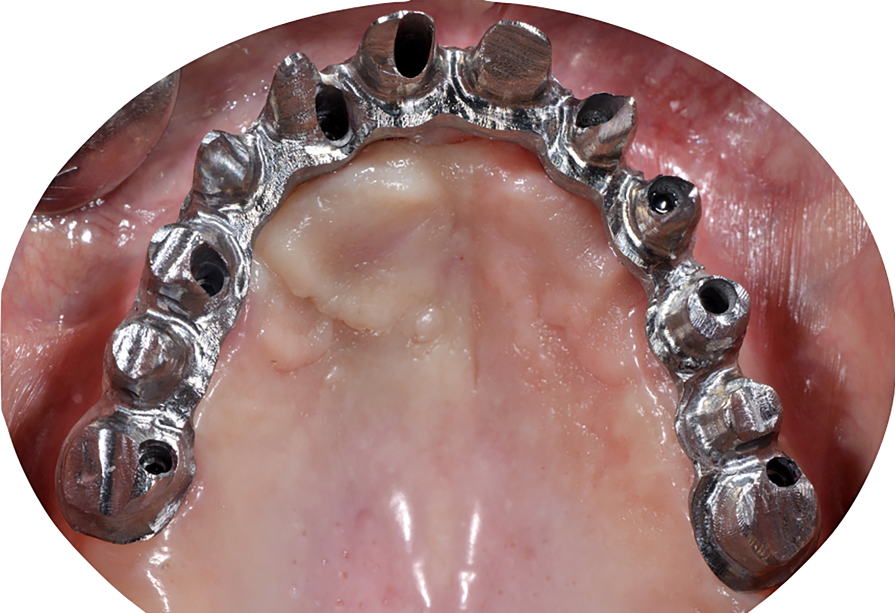

Dopo la rimozione dei denti residui e degli impianti, il paziente è stato immediatamente riabilitato con due protesi totali rimovibili diagnostiche in RP, che hanno migliorato i rapporti intermascellari, la VDO, OB, OJ, fonetica ed estetica. È stato eseguito un tracciato cefalometrico su una radiografia laterale del cranio per una valutazione funzionale iniziale del caso, seguita da una pianificazione protesica virtuale (Fig. 4), quindi radiologica (Fig. 5) e chirurgica. Le caratteristiche delle protesi studiate hanno determinato la pianificazione chirurgica (Smop, SwissMeda) (Fig. 6) e due guide chirurgiche sono state successivamente sinterizzate al laser (2Ingis) (Fig. 7). Gli impianti sono stati quindi posizionati come programmato (Figg. 8, 9), ad eccezione di quelli ai mascellari posteriori, dove è stato eseguito bilateralmente un grande rialzo del seno mascellare (Fig. 10).

Dopo alcuni mesi, altri quattro impianti sono stati inseriti ai mascellari posteriori utilizzando la stessa guida chirurgica (Fig. 23), e dopo altri sei mesi l’arcata superiore era pronta per essere caricata con una riabilitazione protesica fissa su impianti. Tutte le procedure dell’arcata inferiore sono state ripetute per l’arcata superiore (Figg. 24, 25), perfezionando l’ADSD e controllando l’accuratezza dei contatti occlusali.